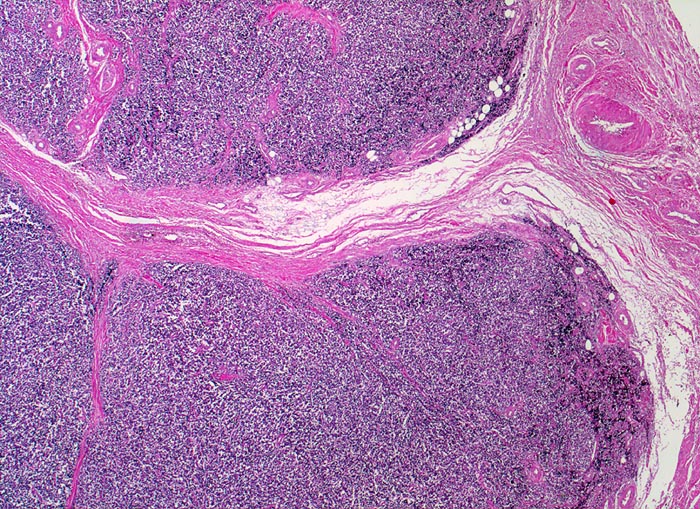

Ewing-Sarkom

Auffallend monotoner dichter Tumorzellrasen mit lobulärer Architektur (d.h. durch Bindegewebssepten abgegrenzte Knoten).

Femuramputat mit festem grauweissem intraossärem feucht-glänzendem Tumorgewebe. Die extraossäre Weichteilkomponente ist weicher und brüchiger. Der Gewebsschnitt stammt aus der extraossären Weichteilkomponente.

Die Ewing Sarkome gehören zur morphologischen Gruppe der "small blue round cell" Tumoren. Zu dieser heterogenen Gruppe aus kleinen runden Zellen bestehenden Tumoren gehören neben den Ewing Sarkomen die verwandten primitiven neuroektodermalen Tumoren (PNET), Rhabdomyosarkome, Neuroblastome, kleinzellige Lymphome, wenig differenzierte und kleinzellige Karzinome, Merkelzellkarzinome, maligne Mesotheliome, kleinzellige Melanome und desmoplastische klein- und rundzellige Tumoren. Weil diese unterschiedlichen Tumoren morphologisch sehr ähnlich sein können, braucht es exakte klinische Angaben und Hilfsuntersuchungen (Spezialfärbungen, Immunhistochemie, molekularbiologischer Nachweis spezifischer zytogenetischer Veränderungen) für eine korrekte Diagnosestellung.

Histologie

25